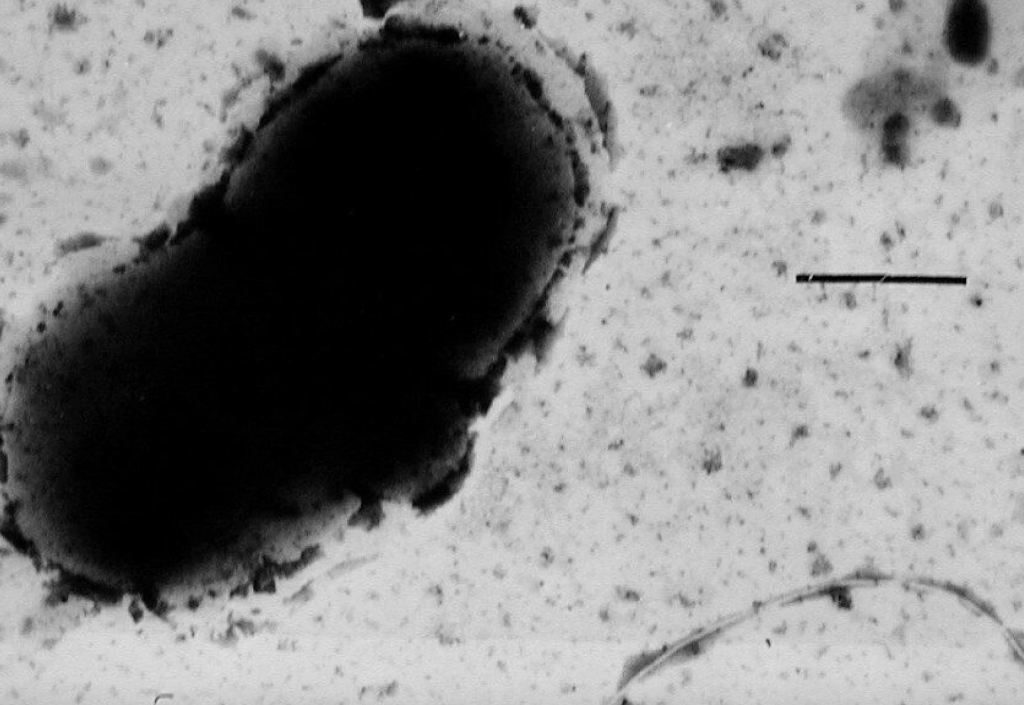

Bakterien kaldes Desulfovibrio og findes almindeligvis i miljøer med vand.

Per Erik Saris ved Universitetet i Helsinki og kolleger har tidligere observeret, at bakterien findes hos mennesker med Parkinson.

I et lille studie fra 2021 målte de niveauet af bakterier i afføringen hos 20 patienter med Parkinson og 20 raske deltagere. Patienterne med Parkinson havde flere af bakterierne i deres prøver.

Højere koncentration var også forbundet med mere alvorlig sygdom. En kinesisk forskergruppe konkluderede det samme i marts.

I det nye studie undersøgte Per Erik Saris og kolleger, hvad der sker med rundorme, når de indtager Desulfovibrio-bakterier. Bakterierne blev taget fra afføringen fra enten raske personer eller patienter med Parkinson.

I det nye studie udvandt forskerne Desulfovibrio-bakterier fra afføringen fra 10 patienter med Parkinson og otte raske personer.